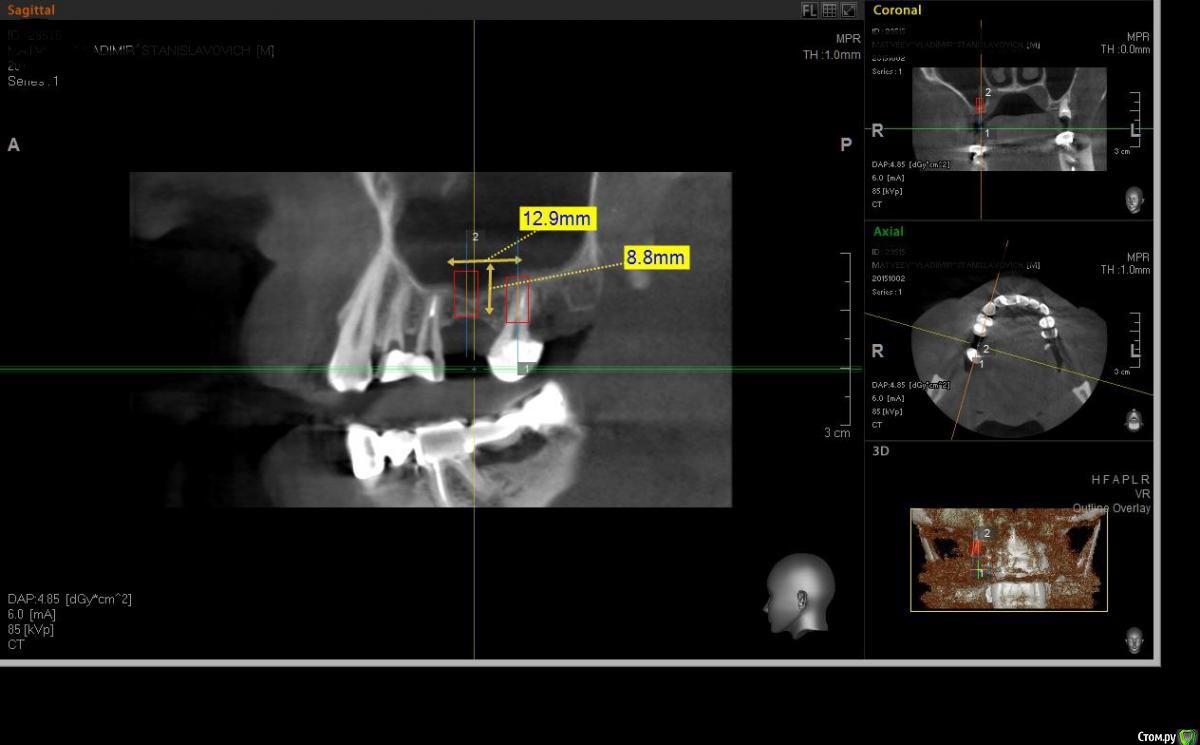

Павел7809 Опубликовано 17 ноября, 2015 Поделиться Опубликовано 17 ноября, 2015 (изменено) Собственно вот я и дошел до полностью самостоятельного открытого с одномоментной установкой 2 имплантиумов. Обращаюсь к Гуру форума так как есть незначительные, но тем не менее важные вопросы не дают покоя....1. Объем графта. Планируется взять 2 мл МП3 хватит ли этого в данной ситуации?2.На срезах четко виднеется сосудик в стенке пазухи на высоте 13 мм. Стоит ли его боятся? И что делать если таки поврежу (просто передавить шипцами чтоли?)3.обязательно ли перекрывать шнейдерову без перфораций мембраной? (в наличии эволюшн тонкая).17 зуба уже нет 2 месЗаранее спасибо! Изменено 17 ноября, 2015 пользователем Павел7809 Ссылка на комментарий